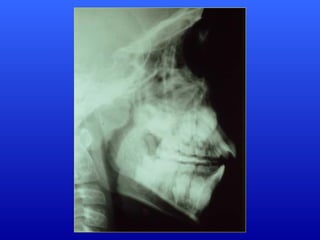

Respirador Bucal Puro:é o individuo com impossibilidade total de respirar pelo nariz. Caracteriza-se resumidamente por: Hipoplasia global da mandíbula, com retrognatismo, hipomentonismo e grande retrusão da arcada inferior Palato ogival; Alongamento, protusão da arcada superior; Lábio superior curto e espesso; Exposição excessiva dos incisivos superiores quando em repouso; Nariz curto vertical.